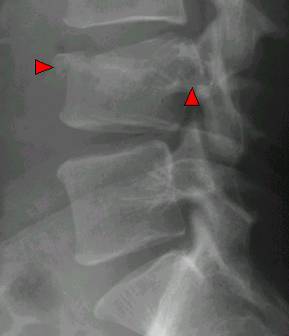

三、脊柱结核:临床特点:1、腰椎多见;2、多累及相邻或多个椎体,附件较少累及

X线表现:1、骨质破坏和脊柱承重 — 椎体塌陷变扁或楔形;2、累及椎体上下缘及邻近软骨板和椎间盘 — 椎间隙变窄或消失,椎体嵌入融合,后突畸形;3、冷脓肿形成,可钙化:腰大肌脓肿(腰椎)、椎旁脓肿(胸椎)、咽后壁脓肿(颈椎)

【影像学检查】X线平片表现以骨质破坏和椎间隙狭窄为主。中心型结核的骨质破坏集中在椎体中央,侧位片比较清楚。很快出现椎体压缩成楔状,前窄后宽。边缘型结核的骨质破坏集中在椎体的上下缘,表现为进行性椎间隙狭窄,并累及邻近两个椎体。可见脊柱侧弯或后凸畸形。椎旁软组织阴影(腰大肌)增宽。